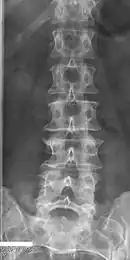

Block vertebrae of the cervical spine (vertebrae 4 and 5). Probably based on degenerative or inflammatory changes.